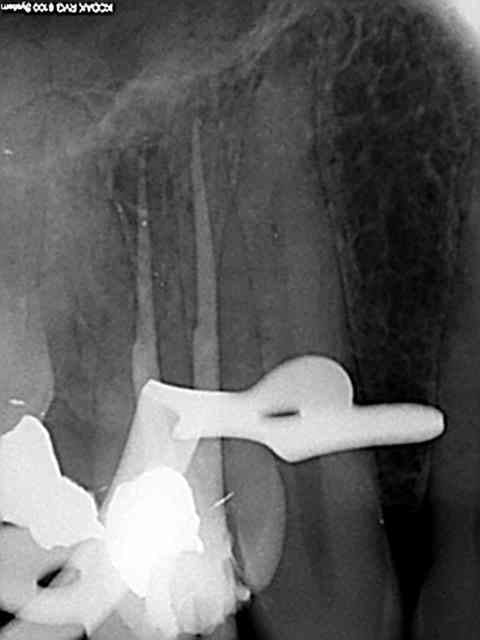

J'ai utilisé le localisateur d'apex , mais bon un radio c'est une radio ...)))

J'ai fait une reprise de TR sur 27 en novembre dernier ; digue, javel, NiTi, pour un bon résultat radio.

Aucun problème de symptomatologie, radio argentique et numérique OK, et découverte forfuite d'un kyste énorme sur la racine vestibulaire de cette dent lors d'un scan pour implant en place de 37.

Radio cone 25 en place etc....)))) j'avoue je pèche dans le etc !)))